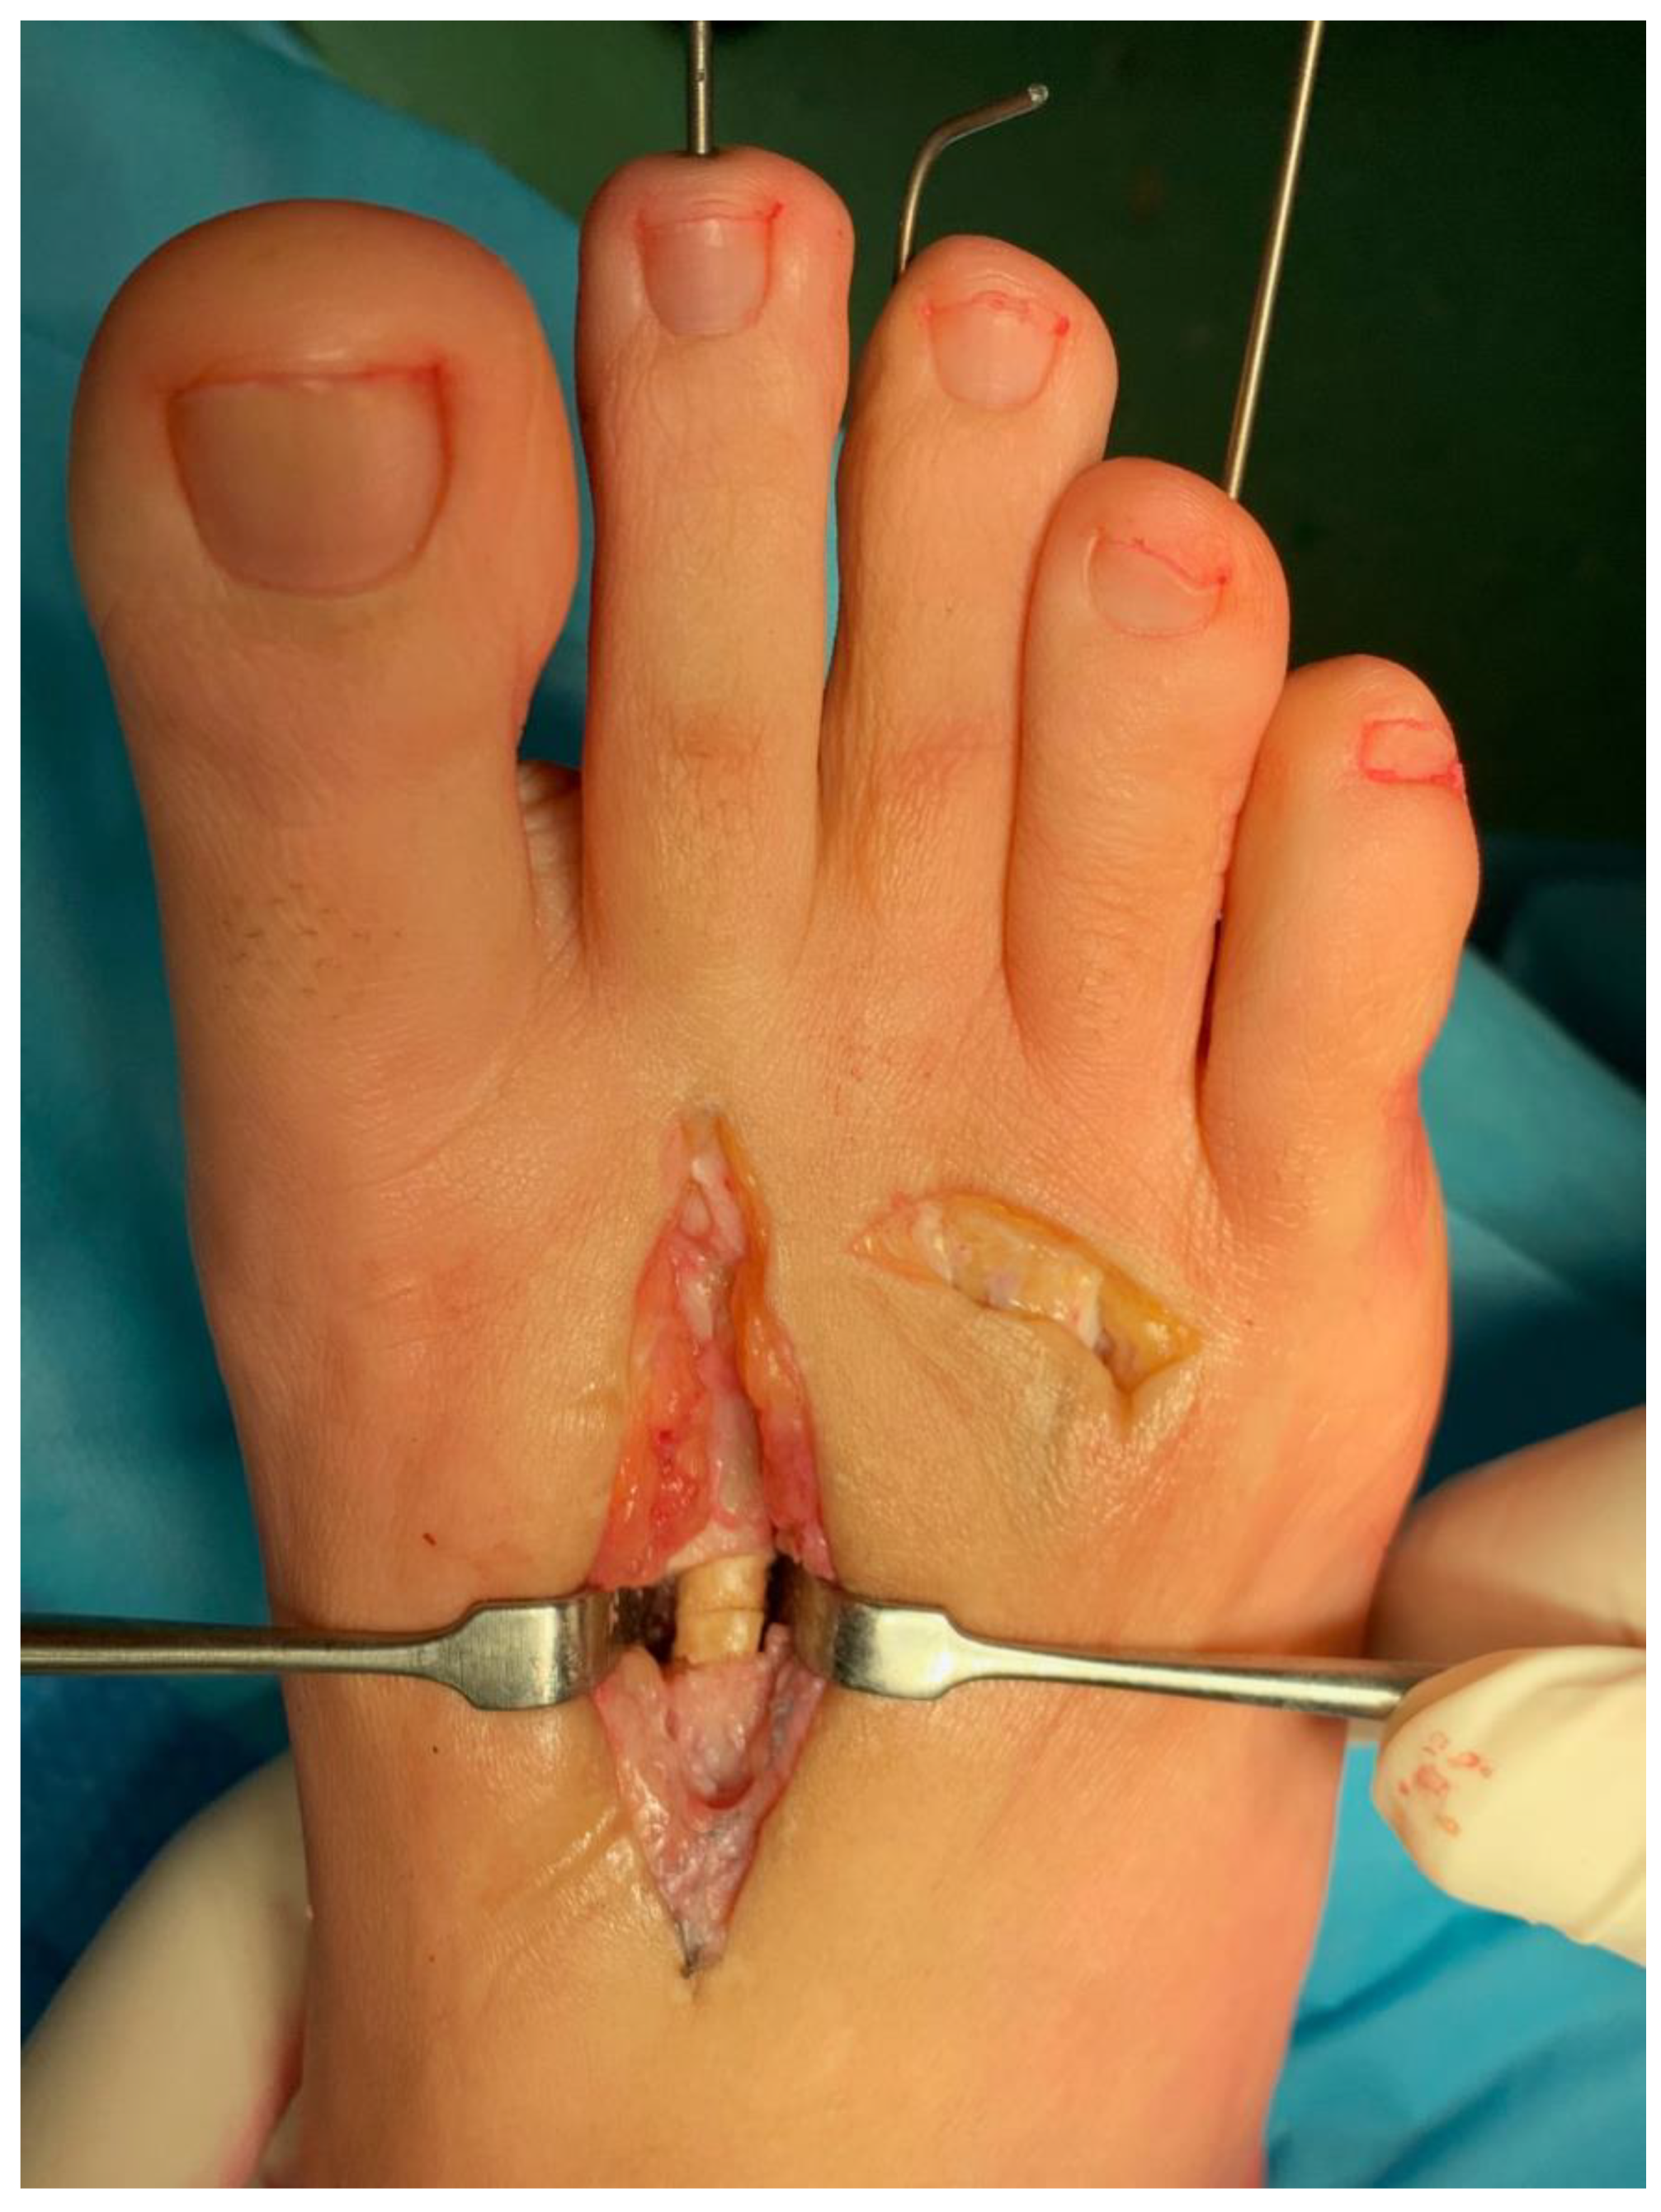

The subsequent X-rays displayed nonunion of the second metatarsal with associated slight metatarsal formula alteration (Figure 1).

Figure 1. Weight-bearing dorsoplantar X-rays of the left foot revealing nonunion of the second metatarsal and a mild alteration in the metatarsal formula.